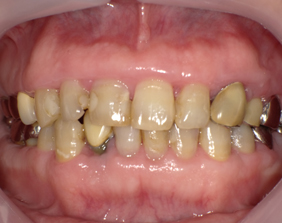

手術前

上下の歯茎が腫れて排膿します。歯磨きするとすぐ出血します。

手術後

上下とも手術しました。もう膿も出ないし出血もしません。